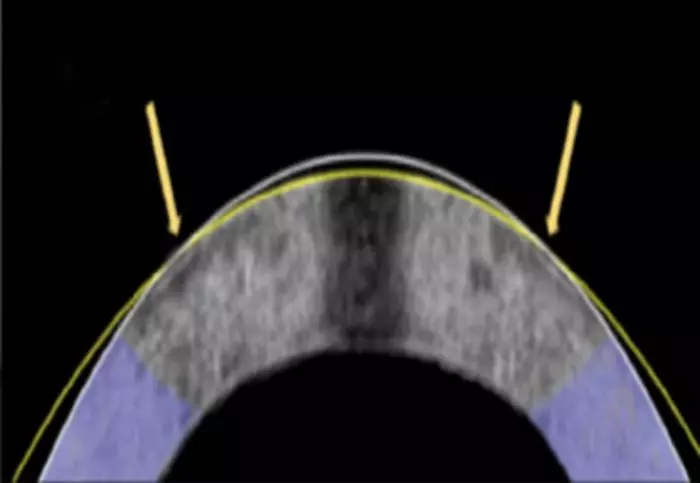

What Hill and colleagues propose is instead working with the composition of the cornea to reshape the dome without removing any material from it. Made primarily of collagen, the cornea maintains its shape thanks to the arrangement of charged molecules and proteins. The researchers discovered that by applying a low-level electrical current through a specially designed platinum "contact lens" electrode, they could change the pH of the tissue, increasing the acidity of the corneal tissue, which would make it pliable just long enough to reshape – like fitting something into a mold. In this case, the mold is the platinum lens.

Then, once the current stops and the pH returns to normal, the cornea hardens again and holds its mold-fitted shape. The whole process takes about a minute, requires no cutting or removal of tissue, and, so far, has shown no structural damage or cell death in the tested samples. And the researchers believe EMR could replace LASIK surgery.

In the study, researchers tested the EMR process on 12 separate rabbit eyeballs, reshaping 10 of them to mimic the corrective effect required for nearsightedness (myopia). After a short exposure to the current, each cornea conformed to the shape built into the electrode "lens", and preliminary measurements showed successful corneal correction – with zero incisions, lasers or trauma to the eye.